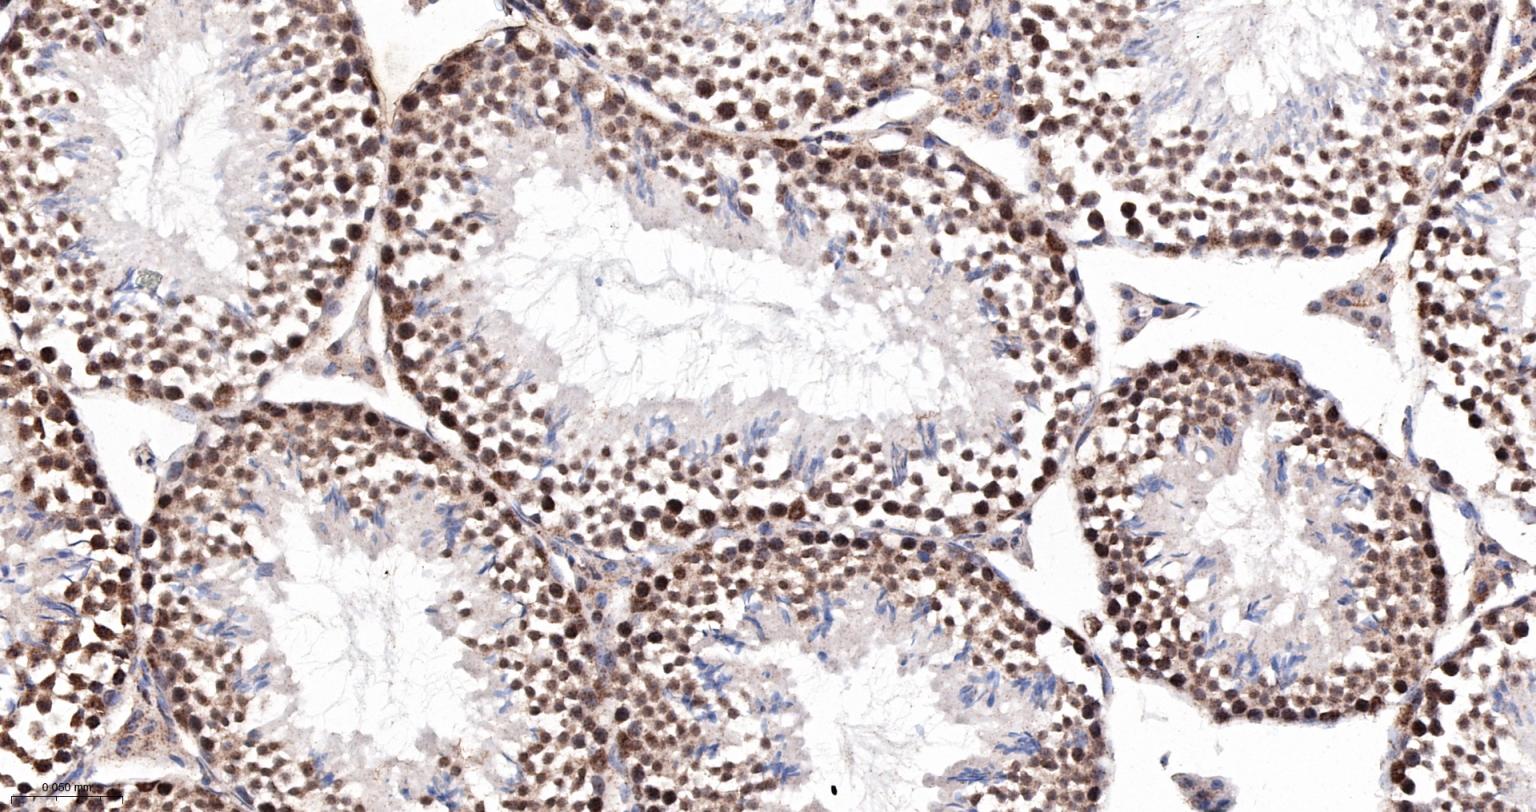

Paraformaldehyde-fixed, paraffin embedded Rat Testicles; Antigen retrieval by boiling in sodium citrate buffer (pH6.0) for 15 min; The section was incubated with MAD2L2 Monoclonal Antibody, Unconjugated (bsm-61670R) at 1:200 overnight at 4°C, followed by conjugation to the bs-0295G-HRP and DAB (C-0010) staining.